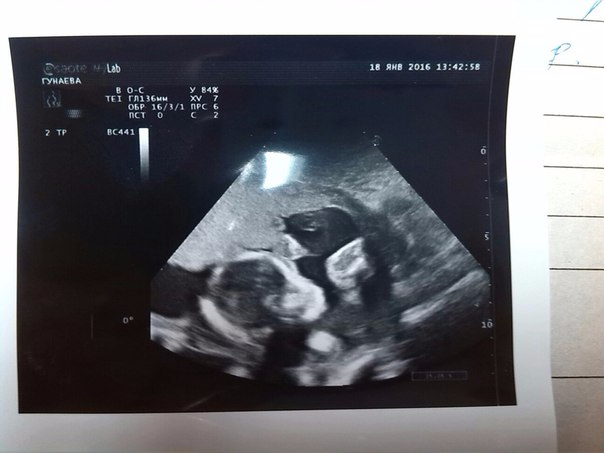

Ааааа ,день Х настал ! У Нас родится СЫН!!! Первые фотографии нашего сыночка !

ААаааа я наконец то дождалась это дняя !!! Смотрели нашу кроху .Мне ничего не показали ,это меня конечно разочаровало ,но папа что то увидел !!))) Главное что все хорошо ! Немного с запозданием первый скрининг у меня ,Я та точно знала день зачатия 16- сентября (11 нед и 5 дней ) Срок 13 и 5 ,молодец доктор с точностью до дня все правильно сказал ! Результат крови узнаю через неделю !